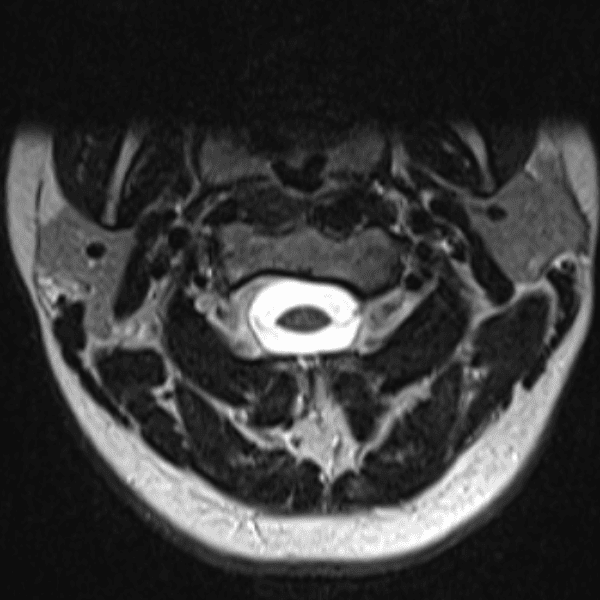

Simulates call by including subtle or difficult cases and some normals.

35 cases